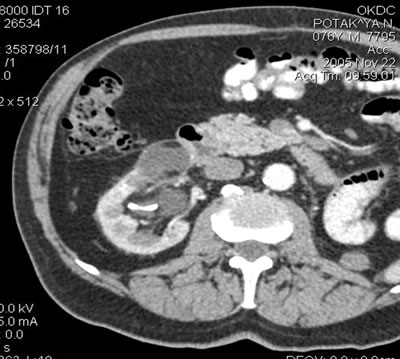

Мониторинг

(10 месяцев) 22 ноября 2005

Спиральная компьютерная томография

(СКТ)

в нижнем сегменте - образование

размером 37х35х27 мм, при болюсном усилении накапление

контрастного вещества (max 21-23 HU)

Спиральная компьютерная

томография (СКТ)